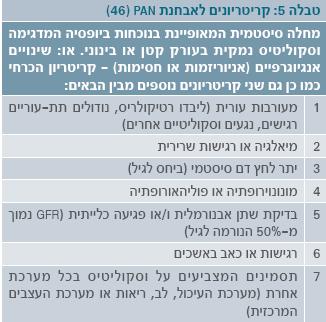

הקריטריונים לאבחנת דלקת רב-עורקית קשרירית מפורטים בטבלה 5. הרגישות והסגוליות של קריטריונים אלו הם 73% ו-100%, בהתאמה[22].